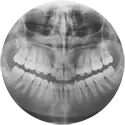

שיניים

רפואת שיניים עוסקת בטיפול בשיניים, חניכיים וברקמות התומכות בהן. מטרתה לשמור על בריאות הפה, למנוע מחלות ולשפר את המראה החיצוני של החיוך.